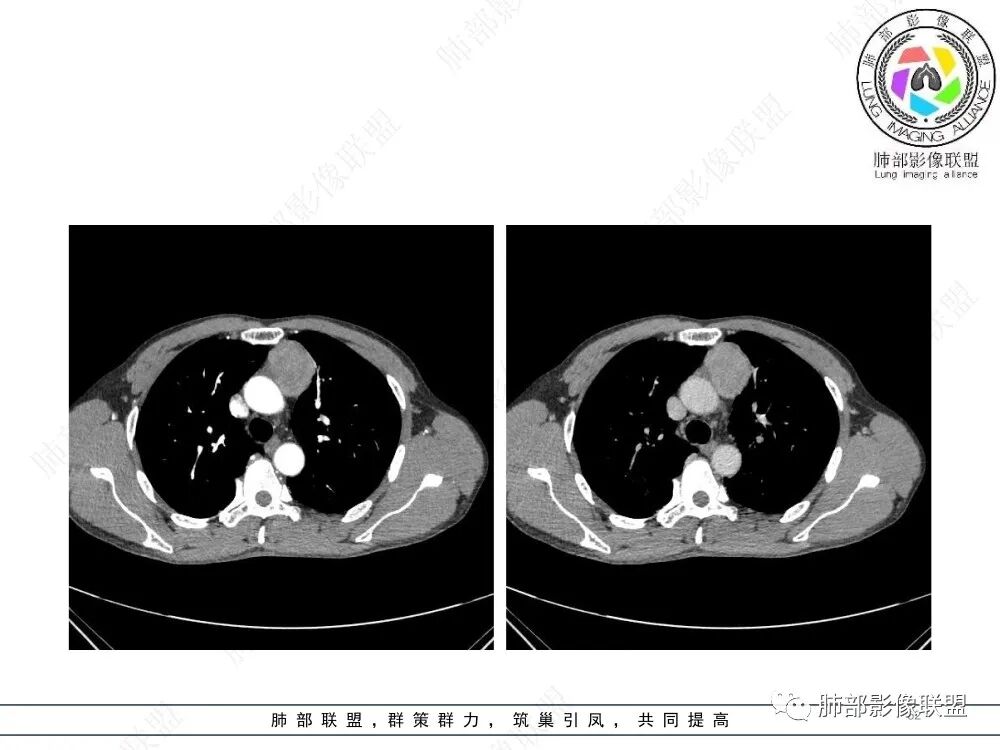

放射小白:男性47岁,前纵隔团块状占位,边界尚清,增强中度强化,内部疑似纤维分隔,常规考虑胸腺瘤可能(A/AB型),鉴别类癌、CD。

瑞欣:中年男性,检验未见明显异常,前纵隔软组织快影,边界清,可见明显强化,首先考虑胸腺瘤,鉴别淋巴瘤,畸胎瘤,生殖细胞瘤。

金豆:晨读:定位前纵隔,膨胀性生长,质地中等,边界清,有浅分叶,中等强化,似乎有裂隙低密度,常规胸腺瘤(B1)。

Yishion:晨读:纵隔占位,偏侧生长,边界清楚,有浅分叶,强化明显,其内似见纤维分隔,常规考虑胸腺瘤(AB型)。

蓝天白云:晨读:47岁男,前纵隔占位,边界清,有浅分叶,中等强化,胸腺瘤(B1)。

宇宙:前纵膈偏左类圆形肿块,边界清晰光整,与大血管脂肪间隙清,密度均匀,轻中度强化,考虑胸腺瘤,A型?鉴别胸腺癌。

玫:男,47岁,咳嗽,咳痰一年,前纵隔软组织密度肿块影,边界清晰,内密度均匀,增强扫描轻度强化,考虑胸腺瘤可能。

周太狼:中年男性,前上纵隔胸腺区软组织团块占位,边界清,增强中度强化,内密度较均匀,常规考虑胸腺瘤。

月亮圆了!:前纵隔包块,边界清,有分叶,密度不均,中等强化,考虑胸腺瘤。

衡妈🇨🇳:中年男性,前纵隔偏左侧实性占位,密度相对均匀,边缘分叶,周围脂肪结构略模糊,增强后动脉期不均匀强化,有低密度区,纤维分隔显示不清。考虑胸腺瘤B1 B2型。

朱伟超:中年男性,前纵膈偏离中线肿块,浅分叶,内有分隔,中等不均匀强化,常规胸腺瘤。

流心明智:男,47,咳嗽、咳痰1年余。胸部CT:前纵膈偏左类圆形肿块,瘤肺界面清晰光整,纵隔侧部分层面絮状影?平扫密度较均匀,增强后轻度强化,内可见宽带及线样低密度分隔。邻近左上肺受压凹陷。考虑胸腺肿瘤,AB型?胸腺Ca?鉴别淋巴瘤、N源性肿瘤、CD等。

2、影像特点:前纵隔偏左侧软组织影,密度相对均匀,未见明显包膜钙化及实质内钙化,局部边缘浅分叶,周围脂肪间隙密度增高、浑浊,未见侵犯大血管、未见纵隔内淋巴结转移、未见侵犯心包内结构、未见胸膜转移结节、未见肿块沿着纵隔胸膜蔓延,未见胸腔积液。增强后动脉期不均匀强化,未见明显纤维分隔。